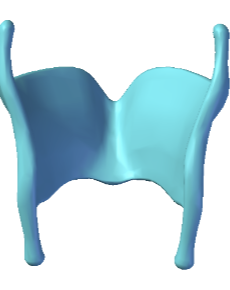

Cricoid Cartilage

Conus elasticus

Vocal ligament